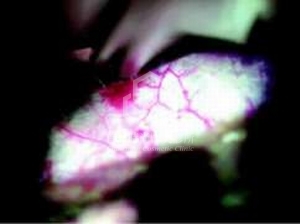

第 二 [ 手 術 後 較 不 疼 痛 ?! ]

手術後疼痛較少的主要原因有二: 一是 胸大肌是否完全”清楚”的剝離: 內視鏡隆乳可以將胸大肌自肋骨上”完全”清楚的剝離, 而不是傳統隆乳用手指, 然後伸入巨大的湯匙狀玻璃器, [瞎子摸象]式粗魯的硬來, 造成胸大肌”部分”剝離, 收縮用力時, 便會亂拉, 縮一通, 因此當然比較痛. 肌肉被完全鬆開後, 便不會亂無章法的收縮, 當然疼痛感大幅降低; 二是肋骨有沒有肋骨膜下出血(sub- or perichondrial hematoma): 外科醫師如果做事開刀不精緻, 其實就像小孩胡亂東闖西撞, 只會造成到處淤青(如右圖, 不管你用傳統或是內視鏡, 只要粗魯行事就會造成出血疼痛), 能不痛嗎? 因此隆乳大師John B. Tebbetts(他過去是研究engineering, 因此術前有超乎一般醫師的精確分析評估, 而非只是[塞入一件東西]這種普通的技術層次而已)即使不用內視鏡隆乳, 照樣不太痛, 原因就出在這裡. 當然還有一些配套措施, 可以使手術後疼痛感減輕, 提高手術滿意度與接受意願. 其實隆乳疼痛感是可以因為外科醫師不莽撞的手術態度而減輕, 也就是回歸到一個醫師的本質.